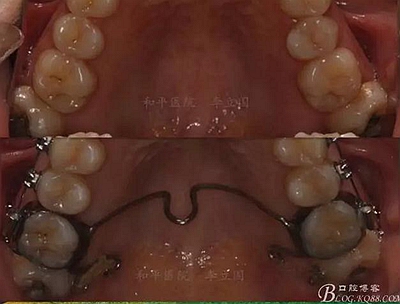

該病例主要為17、27頰側(cè)位同時(shí)伴有伸長(zhǎng),當(dāng)然種植支抗可以解決,但還有簡(jiǎn)單實(shí)用的辦法嗎?如圖,在橫腭桿遠(yuǎn)中延伸出牽引鉤,位置盡量遠(yuǎn)離合平面,7粘舌側(cè)扣,牽引力的方向?yàn)閴旱图吧嘞?,下圖為兩個(gè)月的效果,17已到位,27還未到位。